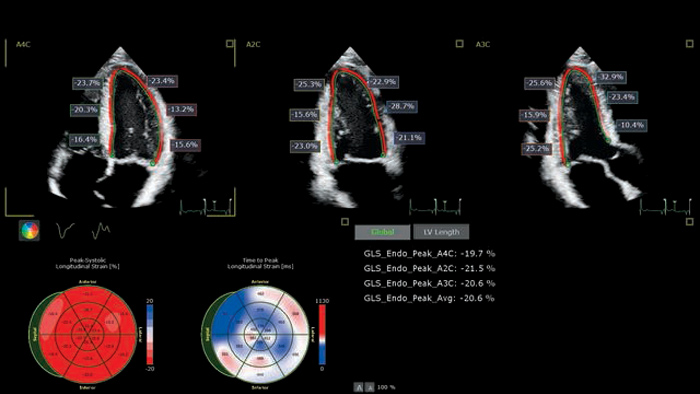

Cardiac imaging modalities support a more confident stratification of cardiovascular toxicity while serving as a powerful baseline reference for treatment and long-term follow-up.